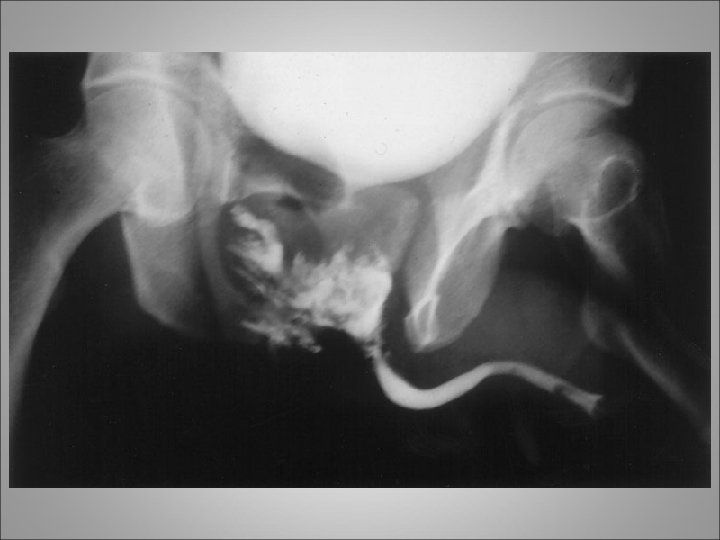

URETHRAL INJURIES • Classified into 2 broad categories based on the anatomical site of the trauma • Mechanism of injury include: blunt trauma such as MVA or falls, penetrating injuries, straddle injuries and Iatrogenic injury like traumatic catheter placement • Posterior urethral injuries commonly associated with pelvic fractures • Anterior urethral injuries come from blunt trauma to the perineum (straddle injuries)

URETHRAL INJURIES • Radiographic or cystoscopic evaluations to rule out this injury are mandatory in the following circumstances: • (1) when the patient presents with the classic triad of findings of a perineal/penile hematoma, blood at the meatus/vaginal introitus, and inability to void • 2) when one or more pubic rami are fractured or symphyseal diastases are present • (3) when radiographic findings suggest a bladder neck injury

Diagnosis • Symptoms include hematuria or inability to void • Physical examination may reveal blood at the meatus or a high-riding prostate gland upon rectal examination. Extravasation of blood along the fascial planes of the perineum is another indication of injury to the urethra • The diagnosis is made by performance of a retrograde urethrogram • "Pie in the sky" findings revealed by cystogram usually indicate urethral disruption

Management • The traditional intervention for patients with posterior urethral injury secondary to pelvic fracture is placement of a suprapubic catheter for bladder drainage and subsequent delayed repair • The suprapubic catheter can be safely placed either percutaneously or via an open approach with a small incision • Ultimate repair can be performed 6 -12 weeks after the event, after the pelvic hematoma has resolved and the patient's orthopedic injuries have stabilized

Management • An attempt at primary realignment of the distraction with a urethral catheter is reasonable in stable patients either acutely or within several days of injury (ie, 5 -7 d post injury) • When the urethral catheter is removed after 4 to 6 weeks, it is imperative to retain a suprapubic catheter because most patients will, despite realignment, develop posterior urethral stenosis

Management • Placement of a catheter across a urethral disruption injury may rarely allow healing without stricture but in most patients, mild stenosis 1 to 2 cm in length develops • Incomplete urethral tears are best treated by stenting with a urethral catheter • There is no evidence that a gentle attempt to place a urethral catheter can convert an incomplete into a complete transection